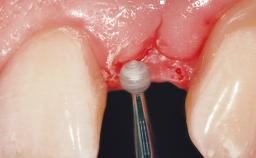

Immediate Flapless Placement of an Implant in a Maxillary Right Lateral Incisor Site

This 43-year-old male patient, a non-smoker, came to our practice because of a fracture of tooth 12 caused by a bicycle accident. Due to the combined para- and infrabony crown and root fracture, tooth extraction, and subsequent implant placement were suggested to the patient as the therapy of choice. The patient had high esthetic expectations with regard to the treatment outcome and asked for an immediate fixed provisional restoration. His individual esthetic risk profile summed up to a medium esthetic risk.

| Soft Tissue Contour and Volume | Ideal |